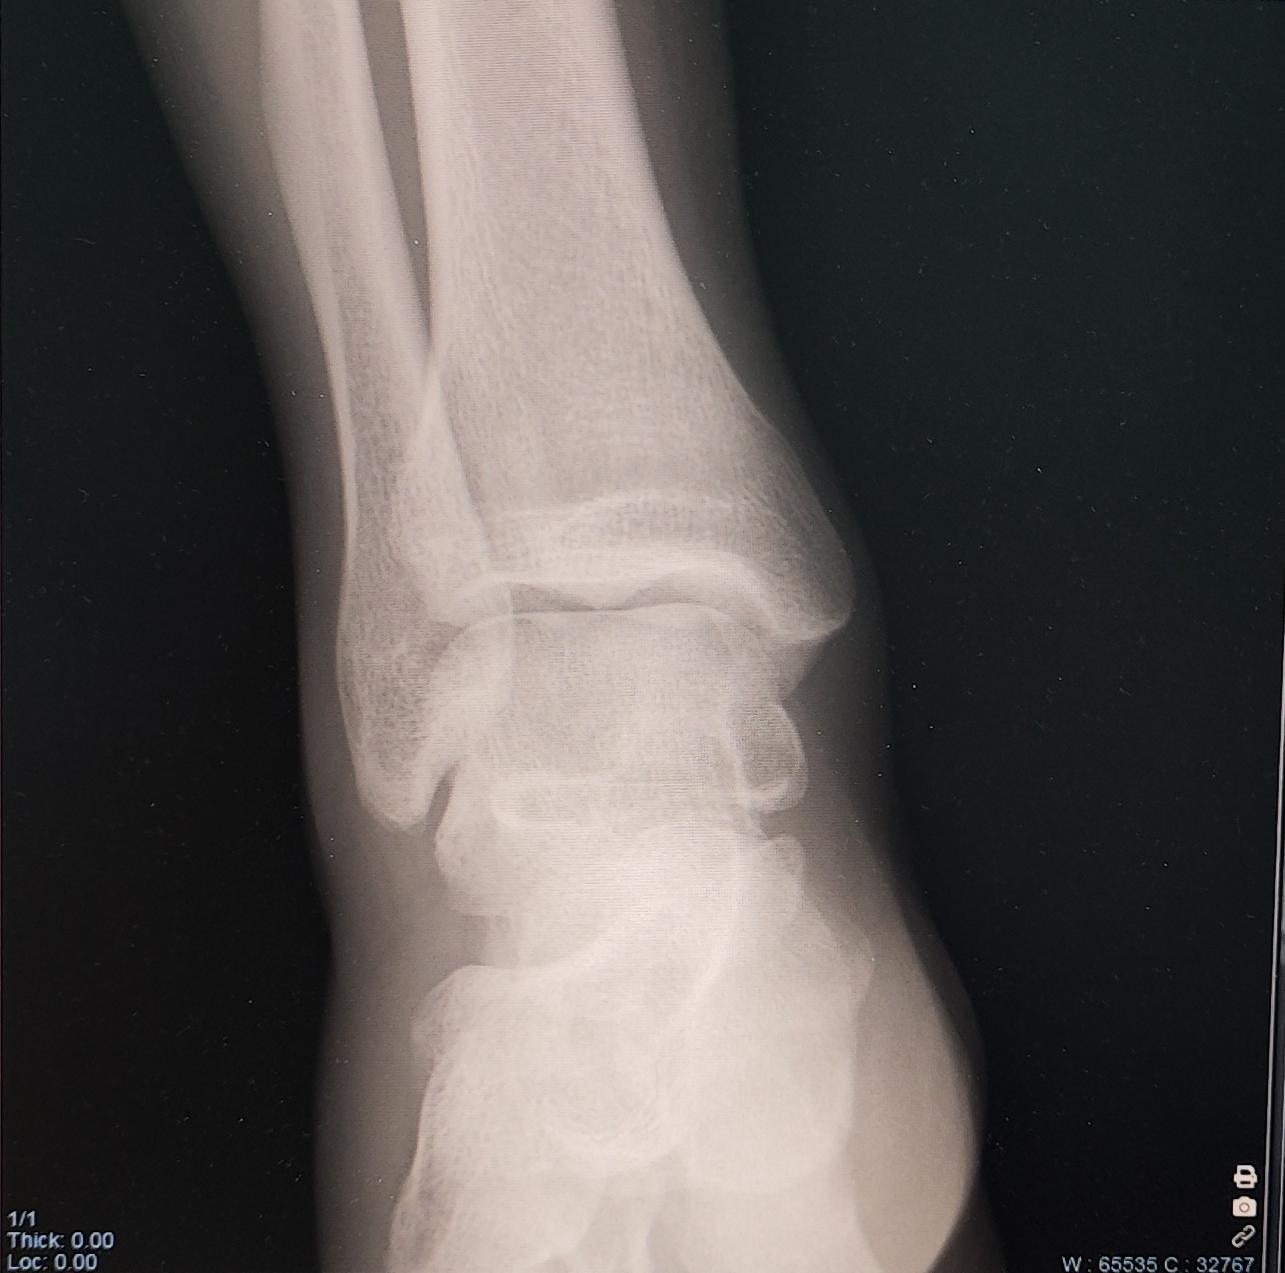

Описание: на Р-граммах левого гс/с в 2х проекциях суставная щель не сужена, субхондральный склероз, краевые остеофиты-не выявлены. По заднему контуру таранной кости определяется наличие дополнительной кости-os trigonum. Заключение:Os trigonum(аномалия развития левой стопы), наиболее вероятно вызывающая синдром компрессии таранной кости.